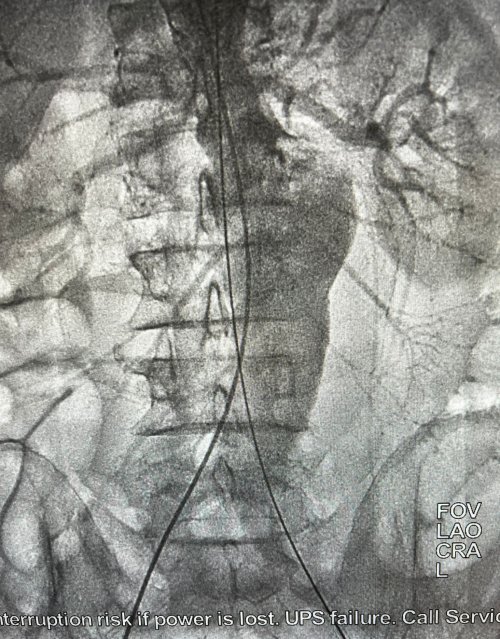

“Hastamız 2016’dan bu yana abdominal aort anevrizması ve hipertansiyon nedeniyle hastanemiz izleminde olan bir hastaydı. Anevrizma çapı 5 santimetrenin altında izlenirken son 2 yıl pandemi nedeniyle kontrole gelmemiş. İlaçlarının düzenlenmesi aksamış, sigara içmeye devam etmiş. Hasta geçtiğimiz günlerde ani tansiyon yüksekliği nedeniyle acil servisimize başvurunca yapılan tetkiklerde karın içi aort damarındaki anevrizma çapı 7.3 cm olarak saptandı. Opr. Dr. Kadir Çeviker ve Opr. Dr. Barış Kemahlı ile birlikte hastamızı değerlendirdik, EVAR (endovasküler aort replasmanı) işlemine karar verdik. Sigara içen bir hastanın açık yöntemle karın damarına yönelik ameliyat riski yüksektir, biz de damarı kapalı yöntemle tamir ettik. Karnı açmadan iki kasıktan atardamar yoluyla girerek anevrizmalı damarını yapay damar ile değiştirdik. Hasta bir gün sonra şifayla taburcu oldu."